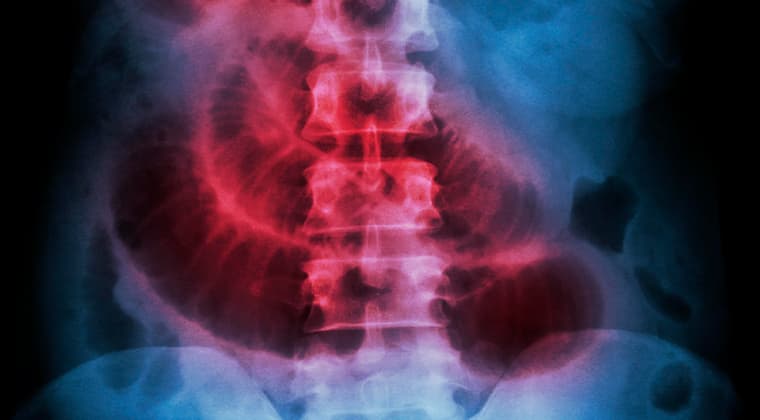

Obstrucción intestinal

Es una condición grave en la que existe un bloqueo que impide el paso normal de alimentos digeridos, líquidos y gases a través del intestino delgado o grueso. Este bloqueo puede ser parcial o total. Cuando el intestino se obstruye, el contenido se acumula detrás del bloqueo, causando distensión, dolor y, si no se trata, puede llevar a complicaciones severas como la perforación intestinal o la falta de riego sanguíneo al intestino (isquemia), que es una emergencia médica. La causa y la extensión del bloqueo determinan el tratamiento, que a menudo requiere cirugía.